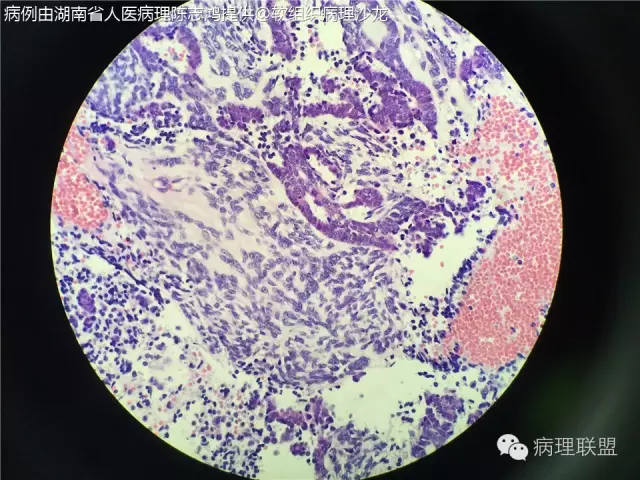

男性,55岁,反复鼻塞伴眼球突出1月余,切除鼻腔肿物(病例由湖南省人医病理陈志鸿提供,致谢!)

@湖南省人医病理陈志鸿 滑膜肉瘤

@镇江四院病理科许跃 我有点小疑惑,书上说腺样结构内是嗜酸性分泌物,但我这一例不是,不知道是否有意义

@河南省医病理 张雷 仔细找找有没有鳞状分化,间质有没有其他分化,这个部位要鉴别畸胎癌肉瘤,多做些免疫组化吧

细胞相对幼稚,要排除下母细胞方面

@广医三院病理江庆萍 就是因为幼稚,所以要考虑畸胎癌肉瘤的鉴别

滑膜肉瘤、癌肉瘤、畸胎样癌肉瘤都应在鉴别诊断之列